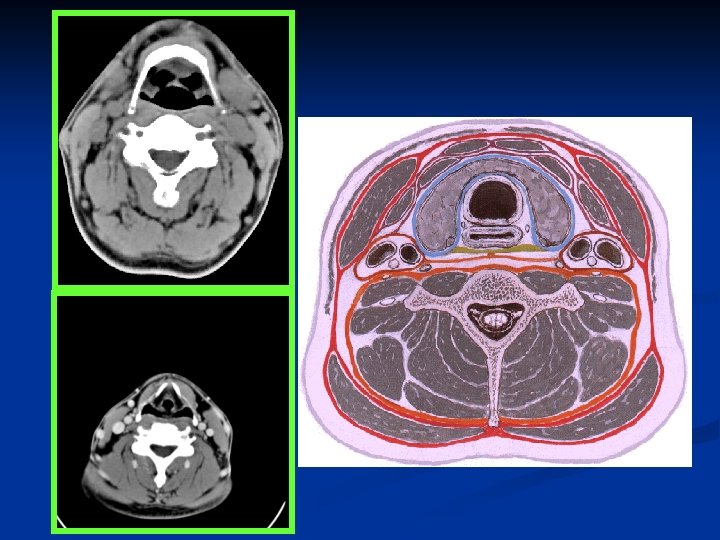

Neck space & vessels

Carotid spaces n Contents: Internal carotid artery Internal jugular vein CN IX, X, XII: nasopharyngeal CS CN X only: oropharyngeal & hypopharyngeal CS Sympathetic plexus Lymph nodes